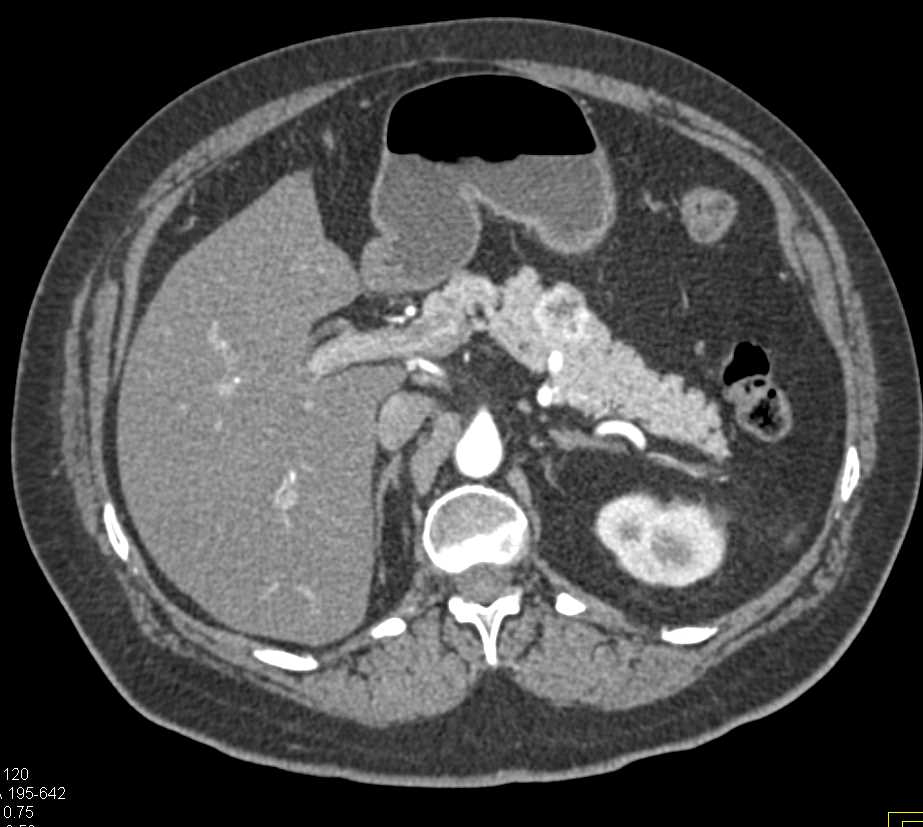

Transitional Cell Carcinoma Right Renal Pelvis